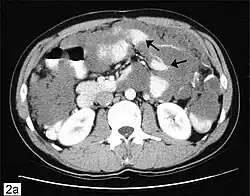

Secondary ovarian cancer

Ovarian cancer can also be a secondary cancer, the result of metastasis from a primary cancer elsewhere in the body.[26] About 5–30% of ovarian cancers are due to metastases, while the rest are primary cancers.[80] Common primary cancers are breast cancer, colon cancer, appendiceal cancer, and stomach cancer (primary gastric cancers that metastasize to the ovary are called Krukenberg tumors).[26] Krukenberg tumors have signet ring cells and mucinous cells.[29] Endometrial cancer and lymphomas can also metastasize to the ovary.[81]